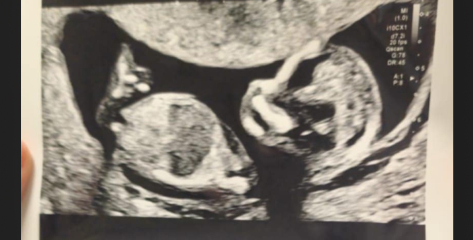

EllieRosesMammy · 21/11/2024 19:02

Boy I think!

There's a Facebook page called "nub predictions" - if you post on there you might get some helpful answers 💜